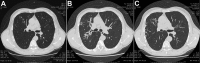

Pulmonary disease caused by Mycobacterium marseillense, Italy